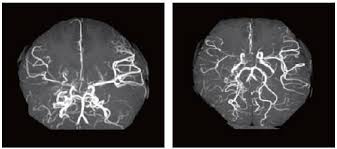

모야모야병은 뇌로 가는 주요 혈관이 점점 좁아지거나 막히는 질환입니다. 혈류가 감소하자 뇌는 이를 보상하기 위해 주변에 가느다란 새로운 혈관을 만들게 되는데, 이 혈관들이 뇌 영상에서 마치 연기처럼 보이기 때문에 일본어로 ‘모야모야’(희미한 연기)라는 이름이 붙었습니다.

◾ 직접 문합술 (Direct Bypass) : 외부의 혈관(두피 동맥)을 뇌혈관과 직접 연결하며 성인에게 주로 시행합니다.

◾ 간접 문합술 (Indirect Bypass) : 근육, 피하지방 등을 뇌에 붙여 혈관 신생 유도하며 소아에게 주로 시행합니다.

▶ 뇌로 가는 혈류를 회복시키고, 장기적인 합병증을 줄이는 데 매우 효과적입니다.